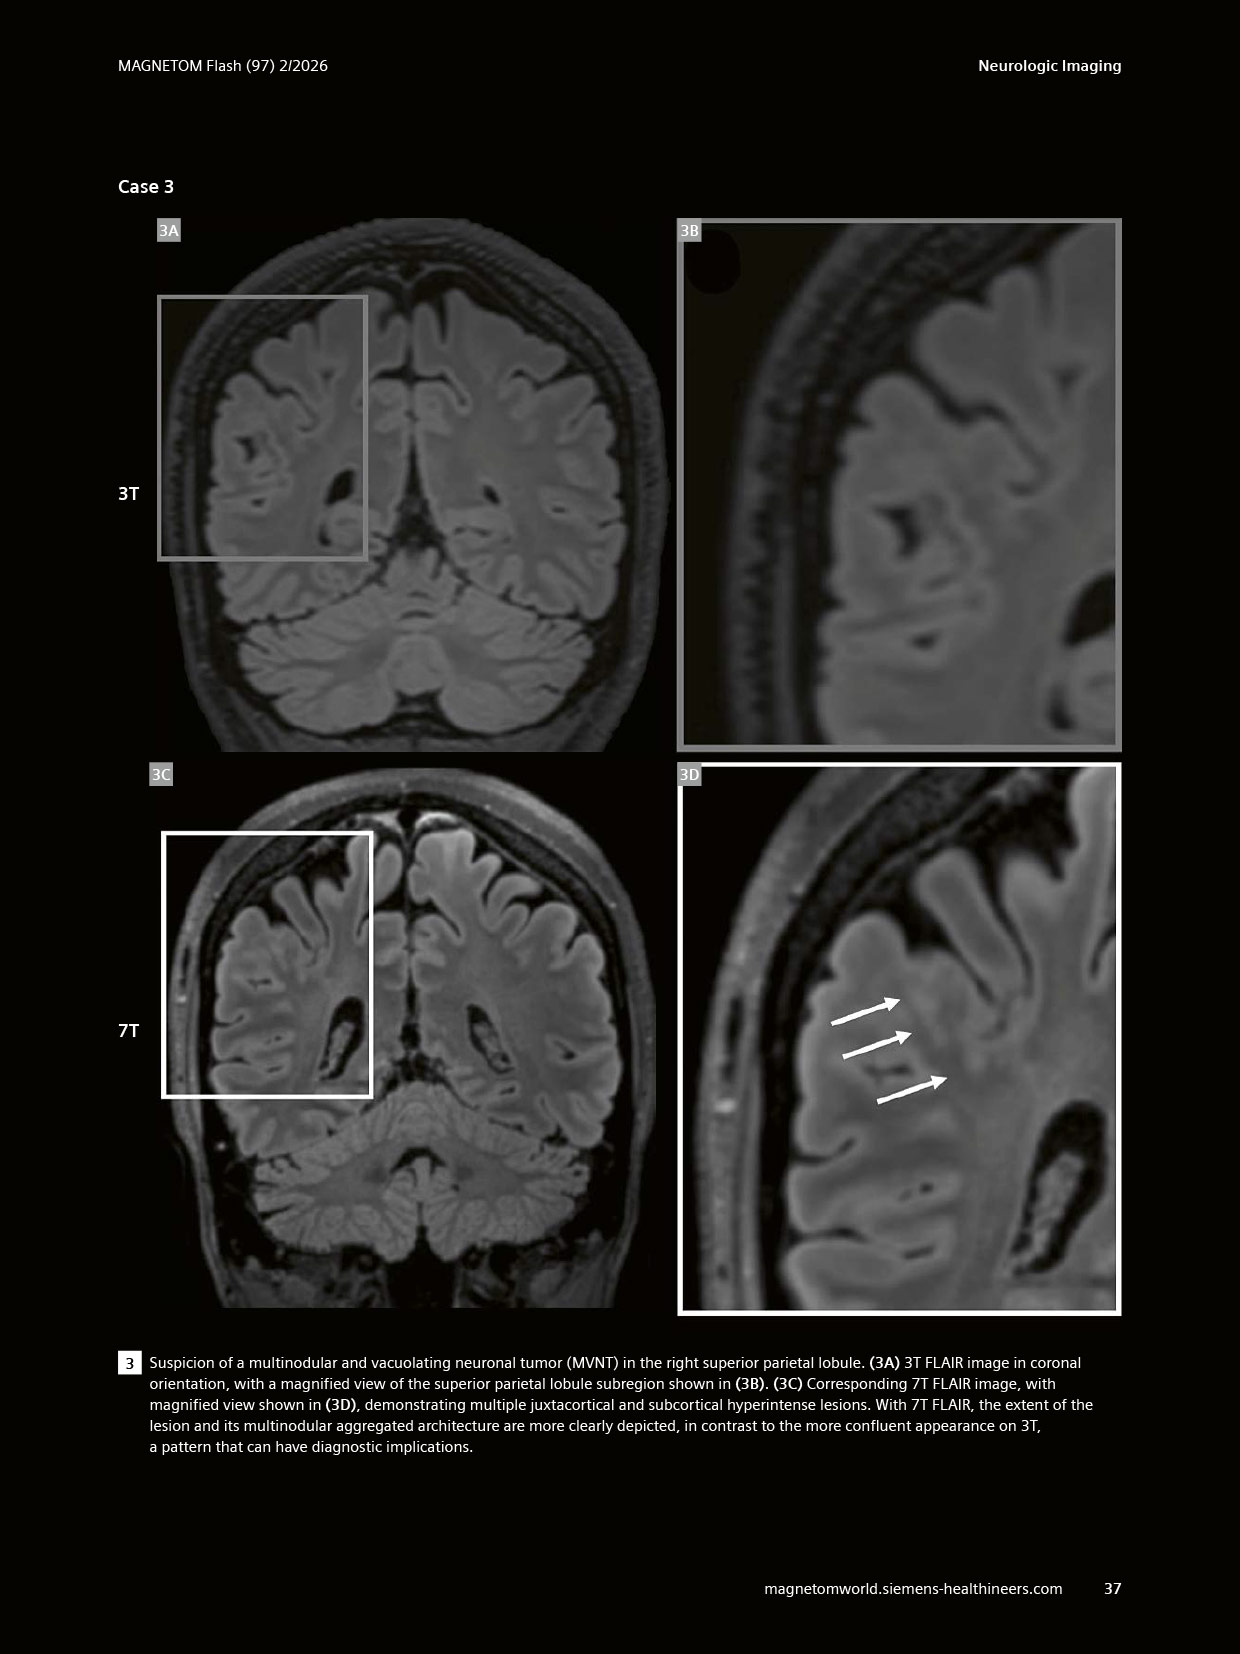

The article ” “Clinical Value of Optimized FLAIR Imaging at 7 Tesla: Neuroimaging Case Examples.” has been featured in MAGNETOM Flash, Issue 97 (2/2026, ISMRM Edition). Co-authored by Emilie Sleight, CIBM MRI EPFL Section and Fréderic Grouiller, CIBM MRI HUG UNIGE Section, Felix Kurtz, HUG, presents our continued commitment to advancing ultra-high-field MRI and its clinical translation.

The article highlights how optimised 7T FLAIR imaging enhances lesion detection and characterisation, with compelling clinical cases demonstrating its added value in neurological disorders such as multiple sclerosis and epilepsy. This work further underscores the growing role of 7T MRI in bridging cutting-edge research and clinical practice.